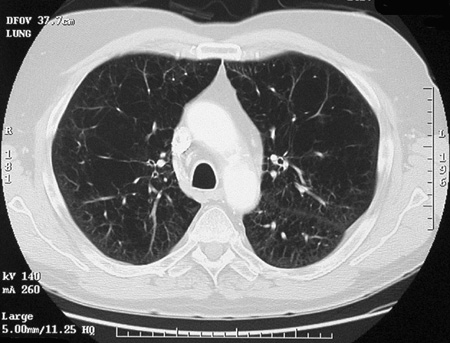

The CT scan of the chest seen here reveals an increase in lung markings with

lucencies

.